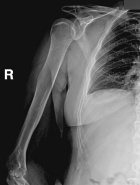

58 year old male with seven week history of increasing right shoulder, arm, and elbow pain and swelling

Zoom image: Radiological image Radiological image.